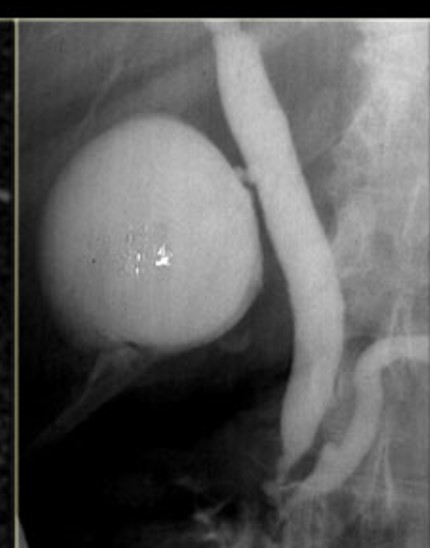

The study is compatible with dilatation of entire extrahepatic bile duct, that’s also known as a true choledochal cyst. Is the type 1 of Todani classification of bile duct cysts.

todani type I

fusiform common bile duct dilation

most common choledochal cyst

tondani type I = fusiform dilation of the CBD